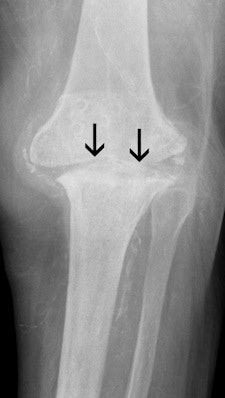

These images show the three most common knee injuries. Left: Osteoarthritis. On the x-ray, the osteoarthritis is clearly recognizable, with the narrowed joint space. Right: Lateral ligament tear. MRI shows the torn lateral ligament (black arrow). The medial ligament (white arrow) is still intact. Copyright of all images: Universitätsklinikum Essen.